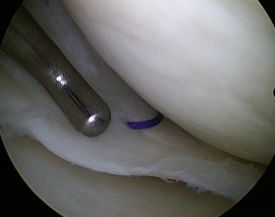

HD-Bilder aus dem Schulter- und Kniegelenk

- zielgenaue Behandlung (gute Sicht dank stark vergrößerter Gelenkdarstellung über HD-Monitor)

Kniegelenk

- Glättung der Knorpeloberfläche

- Spülung des Gelenks

- Microfracturing: Über feine Anbohrungen des Knochens tritt Knochenmark mit Blut- und Stammzellen aus, die eine knorpelähnliche Struktur und Oberfläche auf dem Knorpeldefekt herstellen können.

- Knorpelzelltransplantation